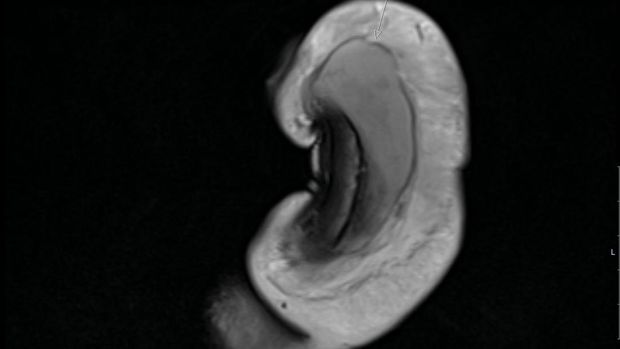

Setelah pemeriksaan, dokter bedah menemukan patah tulang vertikal sepanjang 3 cm di penis, yang dikonfirmasi dengan pemindaian MRI. Ahli urologi yang menangani kasus tersebut mengatakan, luka yang dialami pasien tidak terlihat pada pasien lain.

Penis patah Foto: British Medical Journal (BMJ) |